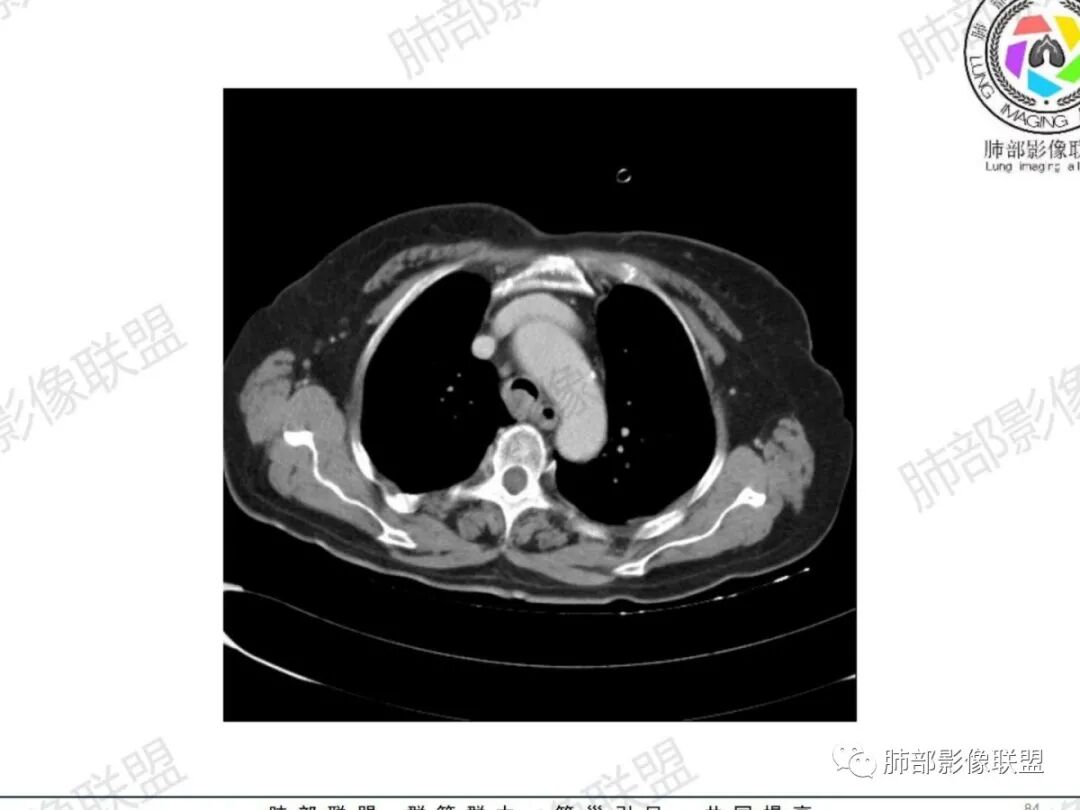

主支气管后缘外可见一实性结节,病变跨支气管管壁生长,部分突向管腔内,病变边缘光滑,平扫密度均匀,增强后尚均匀强化,纵隔淋巴结肿大不明显。

气管结节,不均匀明显强化,跨气管壁,老年女性,考虑恶性——原发:腺样囊性癌、鳞癌、类癌;转移:甲状腺癌?转移。强化部分与甲状腺基本一致,转移瘤可能性大。

主支气管腔内外见软组织肿块,密度不均,不均匀强化,腔内肿块边缘光滑,增强可见不均匀强化,病程长,考虑良性肿瘤性病变,支气管平滑肌瘤?甲状腺左侧叶结节,考虑甲状腺腺瘤或结节性甲状腺肿。

老年女性,慢性病程,反复咳嗽,胸闷2天,支气管内见新生物突向管腔,增强轻中度强化,无明显坏死,左侧甲状腺内见低密度结节,增强示低密度灶内结节状明显强化结节,肺部多发结节,考虑转移,鉴别粘液表皮样癌,腺样囊性癌

宽基底,腔内外,看似边界清楚、光滑, 但是附近气管壁增厚,还是首先要考虑恶性,附近淋巴结也不太放心,因为强化明显

病理类型:甲状腺如果是恶性的,还是要警惕转移瘤;原发的:倾向于恶性,老年女性,表面光滑, 鳞癌几率比较低;腺样囊性癌确实要考虑